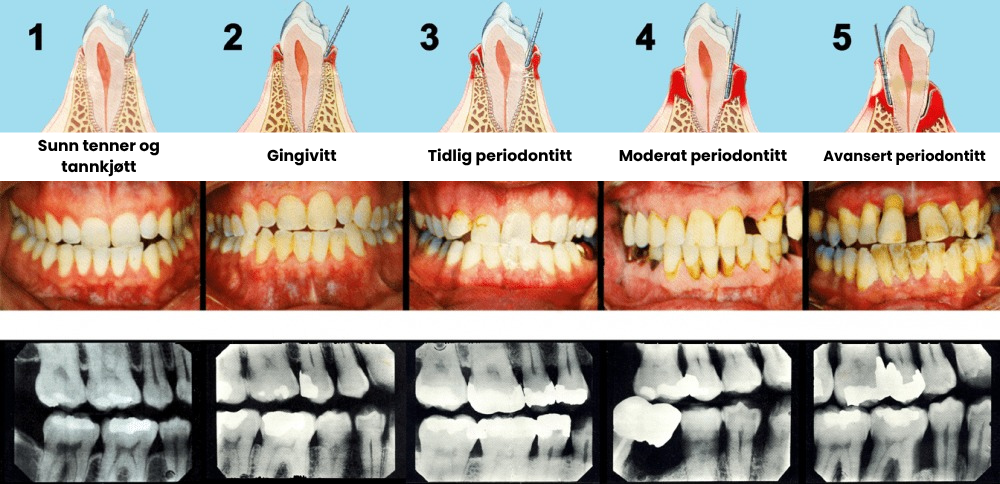

Hvis du svarte "JA" på noen av disse spørsmålene, lider du av gingival tilbakegang – et vanlig munnproblem der tannkjøttvev gradvis går tapt og eksponerer tannrøttene.

Den skjulte faren bak tannkjøtt-tilbakegang

Tilbaketrukket tannkjøtt er mer enn bare et kosmetisk problem – det gjør tennene dine sårbare for hull, infeksjoner og til og med tanntap hvis det ikke behandles.

Når tannkjøttet trekker seg tilbake, dannes det "lommer" langs tannkjøttkanten der bakterier samler seg, og dette gjør problemet verre over tid.